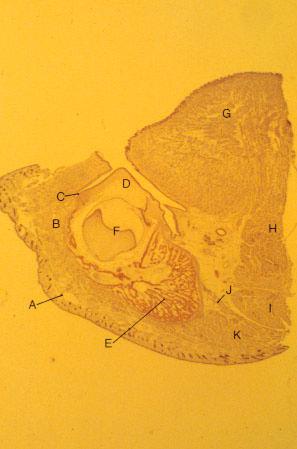

- K-slide 44:

- A. Skin of cheek

- B. Buccinator muscle

- C. Vestibular lamina

- D. [Developing alveolar process]

- E. Mandibular bone

- F. Deciduous molar

- G. Tongue

- H. [Genioglossus muscle]

- I. [Geniohyoid muscle]

- J. [Mylohyoid muscle]

- K. [Anterior belly of digastric muscle]